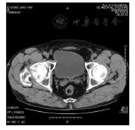

CT image of hip joint after intravenous thrombolysis

患者男性,57岁,既往体健,于2017年2月18日因"脑梗死"收入解放军第三一三医院神经内科。入院前2 h无明显诱因突然头晕后摔倒,右下肢疼痛不适,同时患者家属发现其出现言语不清、不识家人、右侧肢体活动障碍。入院体检:神清,定向力、理解力、计算力障碍,言语不清,额纹对称,右侧鼻唇沟变浅,伸舌不偏;右上肢肌力2级,肌张力正常,右侧肢体痛温觉减退,四肢腱反射对称存在,右侧巴氏征可疑;颈软,克氏征及布氏征阴性,余神经系统体检不合作;右下肢活动受限,外旋畸形,右髋关节压痛。入院后查头颅CT平扫未见异常(图1A),骨盆正位片提示右侧股骨颈骨折(图1B)。查血常规、肝肾功能、凝血功能、离子,均正常。美国国立卫生研究院卒中量表(National Institute of Health stroke scale,NIHSS)评分15分。患者家属强烈要求溶栓治疗,请我院骨科会诊评估后考虑骨折处大量出血可能性不大,遂向患者家属交待溶栓风险并征得其同意后,于发病3.5 h予rt-PA 0.9 mg/kg静脉溶栓,溶栓后患者右侧肢体活动好转(右上肢肌力4级),定向力、理解力基本正常,仍言语不清,NIHSS评分4分。溶栓全过程患者无头痛、出血,右侧髋关节处未见淤血。溶栓24 h复查颅脑CT未见出血、复查髋关节CT未见明显出血(图2)。发病1 d后查MRI证实左侧额颞叶多处新发梗死灶(图3)。溶栓2周后转至我院骨科行右髋关节置换术,手术效果满意。随访3个月,患者言语基本正常,右侧肢体活动可,跛行,改良Rankin量表评分2分。